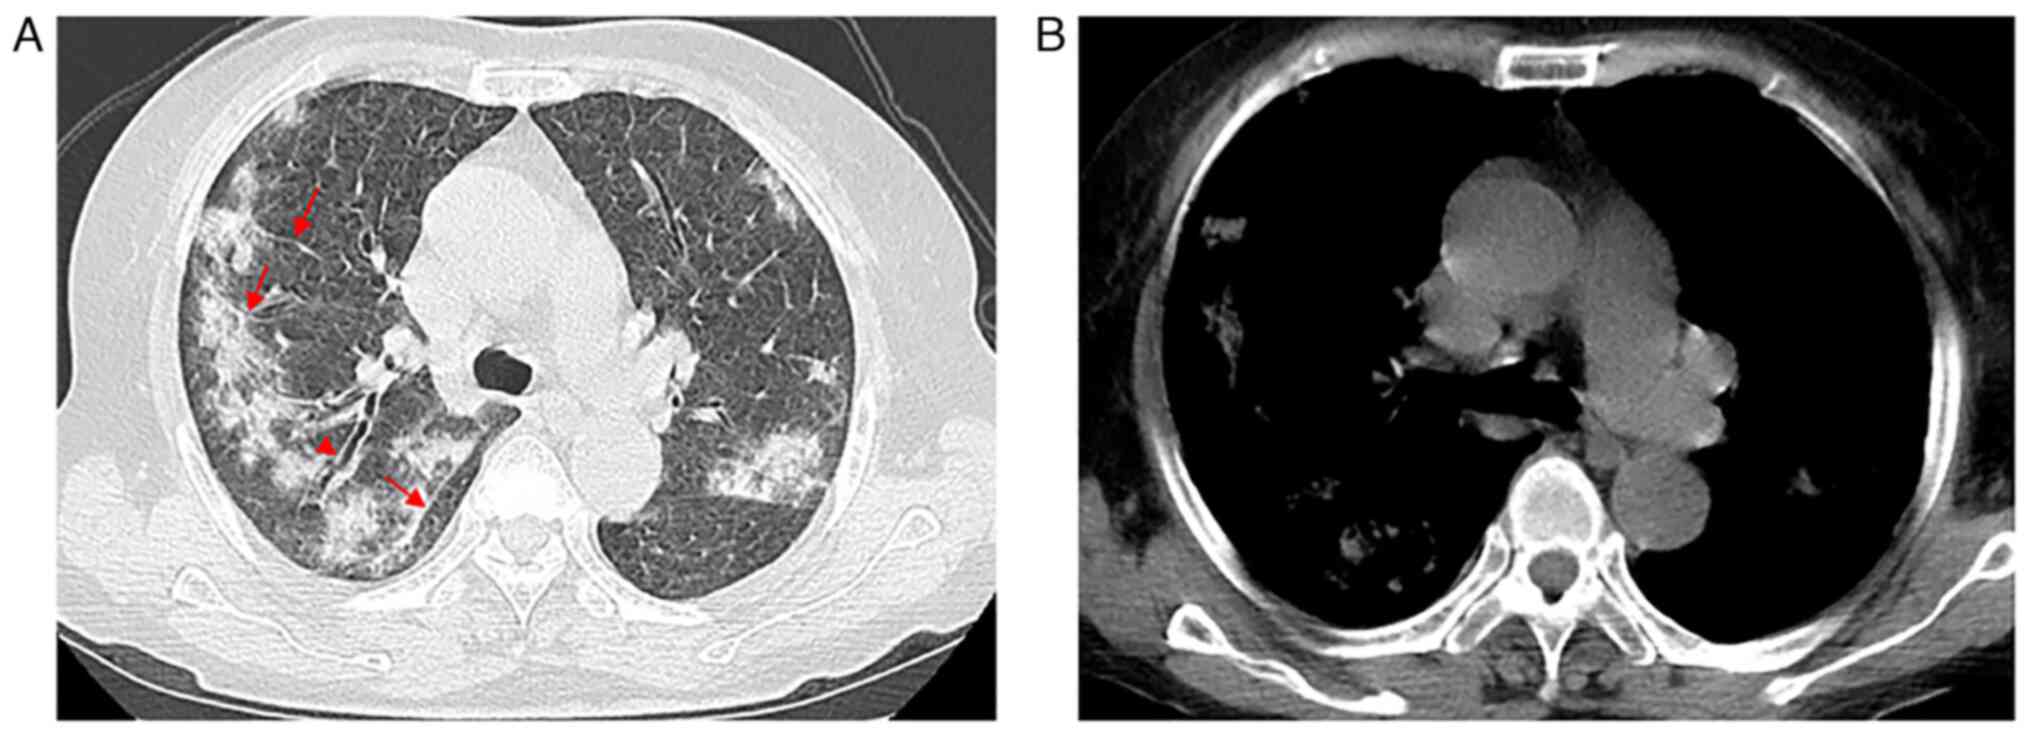

A 68-year-old male with a past medical history of diabetes for ~20 years presented at Nanjing Drum Tower Hospital in May 2012 with a 2-month history of coughing with scantly white sputum, chest tightness, dyspnea on exertion and a recurrent low-grade fever. The patient experienced weight loss (~3 kg) during these 2 months. The patient underwent chest CT. Initial CT imaging evaluation indicated a ground pattern in a mosaic distribution and small centrilobular nodules (Fig. 2A). The patient received anti-inflammatory treatment. However, the symptoms did not significantly improve. Bone marrow aspiration followed by biopsy indicated that the patient had pancytopenia, and a fluorescent in situ hybridization study detected clonal rearrangements of Igκ-VJ and Igκ-V/in, without immunoglobulin heavy locus/BCL2, BCL6 and c-MYC fragmentations or TP53 deletion. TBLB was performed, which demonstrated only a small number of atypical cells. Primary pulmonary IVLBCL was eventually confirmed using open lung biopsy. An incision was made in the fourth intercostal space along the anterior axillary line of the left side of the chest, and lung tissues were respectively excised from the lingual and dorsal segments of the left upper lobe and the dorsal segment of the left lower lobe. The patient started receiving rituximab, cyclophosphamide, doxorubicin, vincristine and prednisolone (R-CHOP) treatment but experienced an allergic reaction after being injected with rituximab (600 mg). Rituximab was removed from the treatment plan, and after improvement with anti-allergy treatment, the patient received 6 cycles of CHOP [1.2 g cyclophosphamide, intravenously (iv) day l; 90 mg doxorubicin, iv day l; 4 mg vincristine, iv day l; 50 mg prednisolone, orally twice per day, days 1–5] treatment, with each cycle lasting for 3 weeks. At completion of the sixth cycle, the disease was in complete remission. As visualized using a CT scan, the bilateral lungs were clear (Fig. 2B).

Figure 2.

Case 2. (A) The image of lung window setting showed ground pattern in a mosaic distribution and small nodules (arrows) with centrilobular. (B) After 6 cycles of treatment, no abnormal shadows were seen in CT scan image

A seventh cycle of chemotherapy began with CHOP (same drug dosage as aforementioned) within 3 months of the completion of the sixth cycle as the patient was admitted to hospital with a fever, cough and chest discomfort. At 2 weeks after discharge after the seventh cycle, an additional three cycles of CHOP (same drug dosage as aforementioned) were provided at 1-week intervals. An additional three cycles of ifosfamide (8 g, iv day 2), carboplatin (500 mg, iv day 2) and etoposide (0.16 g, iv days 1–3) were administered only 1 month after the latest completion of chemotherapy for the recurrence of cough, sputum and fever. The patient's clinical symptoms improved markedly after the treatment. However, the patient was hospitalized again 1 year later due to fever and infection secondary to myelosuppression. Eventually, the treatment failed, and the patient passed away.

Compared with other pulmonary lymphoma, IVLBCL generally does not involve lymphadenopathy or a localizing solid mass, as the lymphomatous cells mainly involve the pulmonary arteries and capillary beds (14). Results of CT assessments are diverse and can be inconspicuous or show GGO and interstitial infiltration (11,12,14). In the cases of the present study, patchy areas of GGO existed on patient presentation and this accentuated the bilateral lung attenuation resulting from pulmonary vascular obstruction. In case 1, the chest HRCT revealed bilateral disease that was pneumonia-like, which progressed partly to consolidation. Due to local interlobular septal thickening along with the thickening of bronchovascular bundles, new GGO indicated lymphatic and hematological spread. The other 3 cases showed bilateral GGOs, micronodules and thickened interlobular septa in the lungs without pleural involvement, which suggested that the disease may spread along lymphatic structures. In case 2, the pulmonary shadows completely disappeared after a short-term chemotherapy schedule, which supported the diagnosis of IVLBCL. The etiology of GGO (heterogeneous and partially consolidated) in all four patients remains unclear. Malignant cells may invade the alveolar space, resulting in consolidation (increased density) on CT imaging. Increased diffuse density in bilateral lungs with GGOs and thickening of interstitial septum needs to be distinguished from non-neoplastic lesions, such as interstitial diseases and mechanical pneumonia, which may also present as progressive dyspnea with cough and other manifestations of obstructive ventilation. TBLB and bronchoalveolar lavage fluid can be used to aid diagnosis. Undoubtably, IVLBCL needs to be differentiated from venous thromboembolism and other intravascular malignancies of the lung, including lymphomatoid granulomatosis, angiocentric lymphoma and pulmonary involvement by acute and chronic lymphocytic leukemias (3). At this point of the patient examination, the clinical manifestations and CT characteristics may be non-specific, and immunohistochemistry will provide great help for the correct diagnosis.